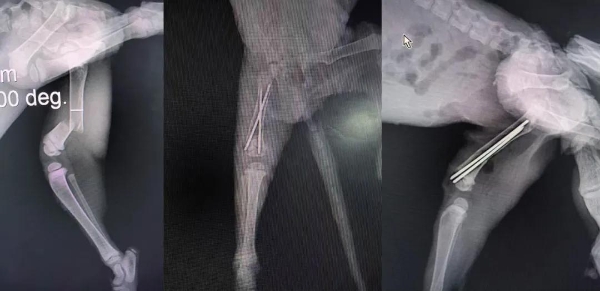

病例名称:猫股骨骨折

患宠品种:田园猫

患宠名字:小流浪

患宠年龄:不足两个月

检查情况:患猫为0.5kg小流浪猫,被好心人发现后送医,由于年龄较小体重较轻,骨密度低,麻醉和手术都具有很大挑战性,如手术未能成功,很难进行二次手术。

诊断治疗:经过触诊、影像检查等,确诊猫咪为股骨骨折,随后进行手术治疗。手术顺利完成,预后良好。